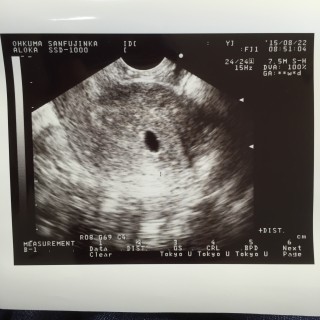

3回の流産をして、今度こそと信じるのみ!胎嚢は予想を超えた10.1㎜でした。 次の一週間が長~い。